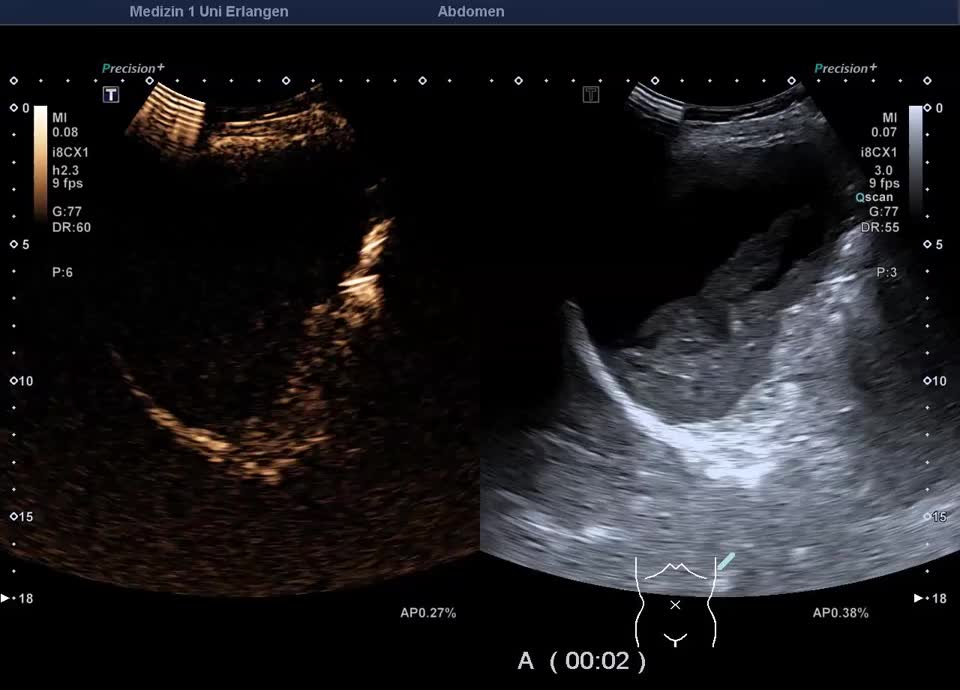

Kasuistik: 57-jährige Patientin mit einer Granulomatose mit Polyangiitis mit unklarer Leberwerterhöhung (ohne abdominelle Symptomatik). Im Ultraschall zeigt sich ein überraschender Milzbefund: Die Milz stellt sich großteils liquide dar, mit nur einem geringen Anteil soliden Gewebes, die Milzkapsel ist intakt. Die Kontrastmittelsonographie zeigt wenig erhaltenes und kontrastiertes Milzparenchym, ohne KM-Austritt in die flüssigen Anteile. Ein Trauma ist auf explizite Nachfrage nicht erinnerlich. Der Befund entspricht dem seltenen Fall einer asymptomatischen subtotalen Milznekrose, am ehesten im Rahmen einer nekrotisierenden Vaskulitis.